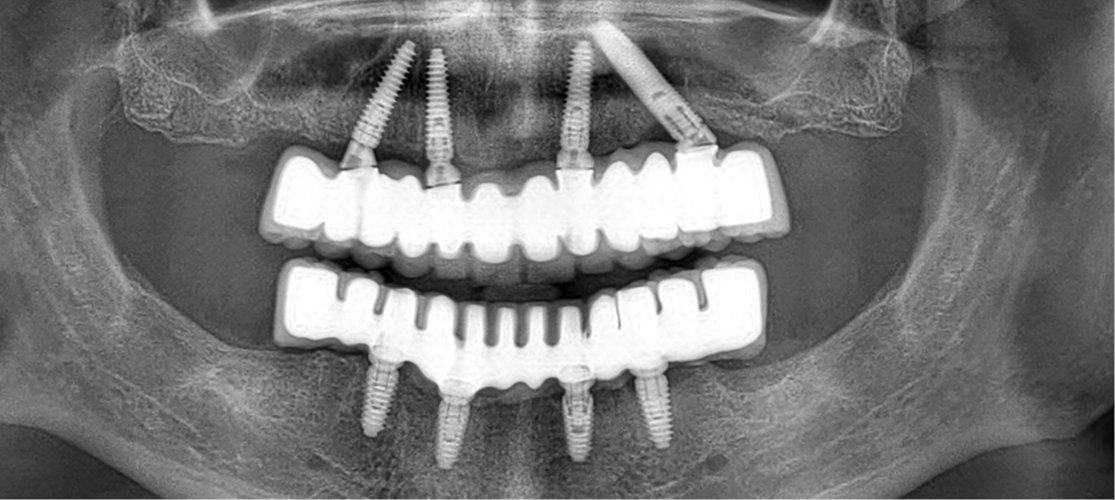

The All on 4 treatment is a dental implant procedure designed to provide a full arch of teeth using only four implants.

The All on 4 treatment concept was developed to provide edentulous (toothless) patients with an efficient and effective solution using fewer implants than traditional methods. This treatment can be used for patients who have lost most or all of their teeth in one or both arches (upper or lower jaw).

• Implant Placement: Four titanium implants are strategically placed in the jaw. Two implants are positioned at the front of the jaw, and two are placed at an angle in the back to maximize bone use and provide stability.

The All-on-4 procedure involves placing four dental implants in each jaw to support a full arch of prosthetic teeth. Two implants are placed vertically in the front and two are placed at an angle in the back to maximize contact with the bone.